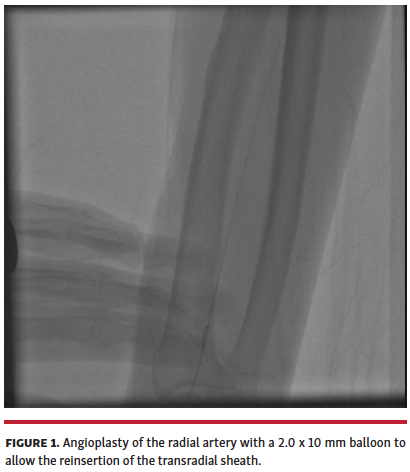

A 92-year-old male patient was scheduled for coronary angiography at our center because of an acute coronary syndrome. The right radial artery had good pulsatility, although the tactile feeling indicated a vessel with some small calcific nodules resembling rosary beads. After puncture, the 0.021˝ dedicated wire of the 6 Fr transradial Glidesheath (Terumo) did not pass through the artery despite a good pulsatile blood flow from the right radial artery. We then used a 0.014˝ Sion Blue coronary wire (Asahi Intecc), which was easily advanced in the right radial artery. However, although we performed a small skin cut around the coronary wire, the sheath dilator was stuck in the proximal radial artery wall. At this point, we performed a balloon angioplasty in the right radial artery with a 2.0 x 10 mm semicompliant balloon with 4 inflations up to 8 atm (Figure 1). After this maneuver, we successfully advanced the sheath into the right radial artery to perform coronary angiography without shifting to an alternative arterial approach. No hematoma, pseudoaneurysm, or compartment syndrome occurred. The following day, the patient was discharged.

The inability to advance the dedicated wire of the transradial sheath in a radial artery with a good pulsatile blood flow is a very rare event. In this case, the advancement of a high-performance 0.014˝ coronary wire is the only option to gain the vessel. Then, if the transradial sheath is stuck in the proximal radial artery wall, balloon angioplasty of the radial artery may allow successful reinsertion of the transradial sheath. This technique allows the preservation of radial artery access, avoiding a shift to an alternative arterial approach.